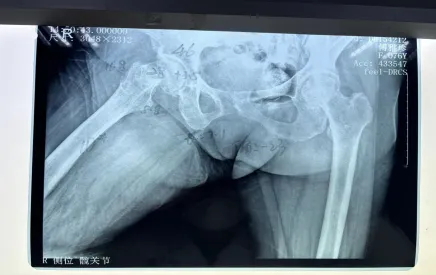

但不幸再次降臨,阿婆在家起床時不慎摔倒,右髖部疼痛難忍,經(jīng)過醫(yī)院檢查后確認,傅阿婆為右側(cè)股骨頸骨折。

阿婆住院后,羅院長立馬聯(lián)系內(nèi)科和麻醉科專家來會診,積極調(diào)整阿婆各項不理想指標,盡量將手術風險降到最低。羅院長還針對阿婆病情特殊情況進行一對一的計算機三維精準規(guī)劃,精心打造出詳細的手術方案,經(jīng)過羅院長手術團隊的努力,阿婆成功完成了機器人輔助下右側(cè)人工雙動股骨頭置換術。